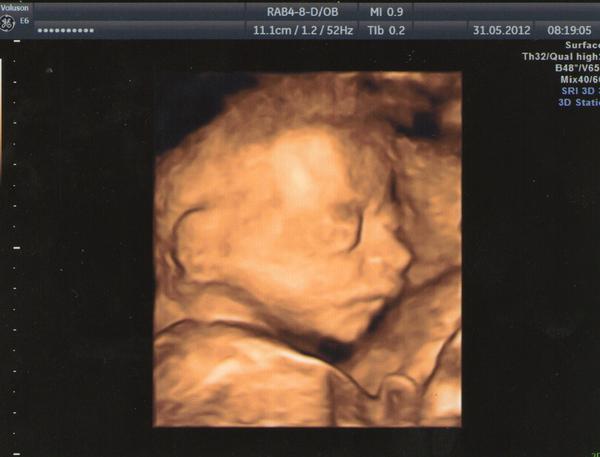

Mám problém,který mi nedokážou vysvětlit ani lékaři.S tímto se prý ještě nesetkali.Již 12 let podstupujeme IVF,máme jednoho dvouletého chlapce,ale za sebou i několik potratů.Provedeno x vyšetření,ale bez výsledku.Co se ,ale stále opakuje, je vždy na začátku těhotenství ve spánku prožitý orgasmus,který se ale následně zmnění v šílený stah dělohy.Je neskutečně bolestivý,jakoby vám někdo rval dělohu z těla.Při následné kontrole ultz.,embrio žije se srdeční akcí.Při další kontrole bez SA a embrio vypadá jakoby v jiné poloze.Jednou spadlé u děložní branky.Po tomto prodělaném nočním stahu již vím,že zase potratím.Nikdy se nespletu.Při těhotenství ,které dopadlo porodem,se tento stav také objevil,ale bez bolesti.Vypadalo to jako klasický orgasmus.

@danissa Jo ,tak nějak se to stává.Předposlední i poslední potrat probíhal tak nějak.Kolem 8 týdne se to stalo a ve12 týdnu už nebilo srdíčko.Teď naposledy se mi to stalo dokonce třikrát.Já jsem si to vždycky trochu myslela,že ten orgasmus souvisí s těmi potraty.Aleď jsem si skoro jistá.Ono možná záleží na tom jak sylný je ten stah.U mě je to ukrutné.Jakoby mi chtěl tu dělohu někdo vyrvat z těla.Myslím si ,že to to embrio nějak poškodí,nebo trošičku vydloubne ze sliznice.Doktor do té doby vždycky říká,že plod vypadá tak jak má.Pak se najednou něco zkazí.Teď se treprve Caru chystám,takže jsem to ještě s doc.neprobírala.Jenom než mě odeslal ke svému gyn.tak jsem se ho na to ptala,protože to u mě zrovna proběhlo.Ale na ultr.vypadalo všechno OK,takže to moc neřešil.Jenom říkal taky to,že je děl.sliz.moc prokrvená.